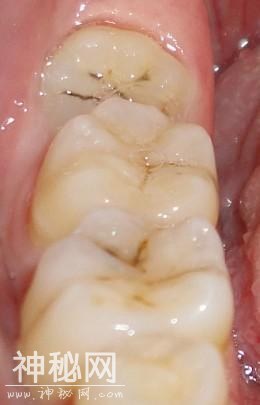

1、智齿有蛀牙的情况:

如果智齿出现了蛀牙的情况的话,是要马上拔除的,智齿是一个比较容易发生蛀牙的部位,主要是其位置比较靠近里面,我们平时刷牙很难清洁到的缘故,所以容易产生蛀牙。